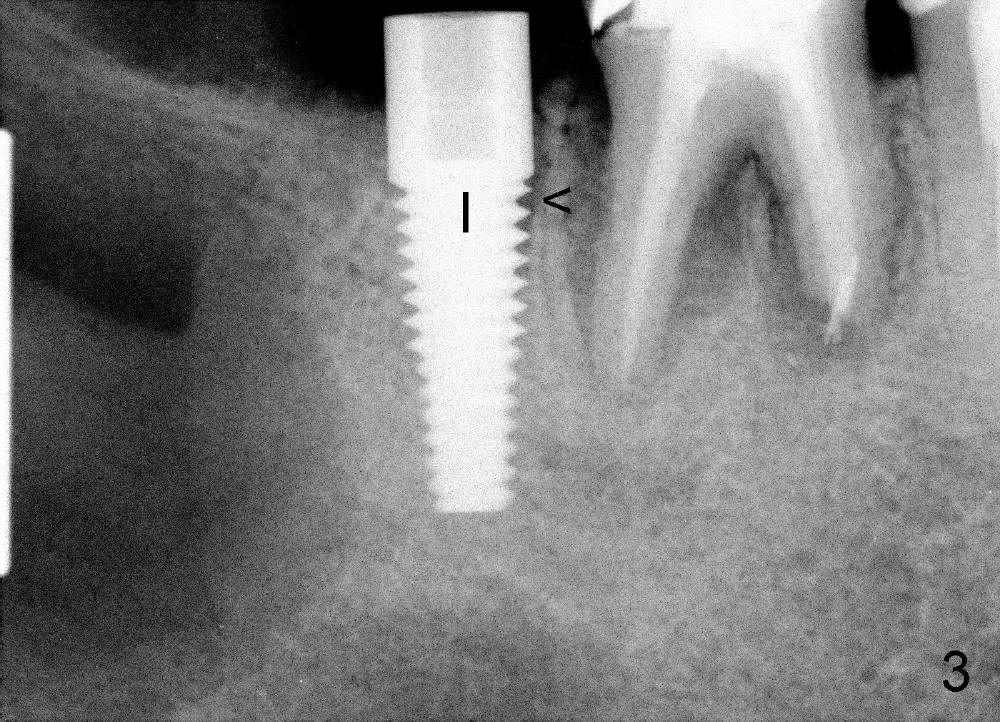

Immediately post extraction and cyst enucleation, osteotomy is formed in the mesial socket of the 2nd molar surrounded by intact bone (Fig.2 (T: 5x17 mm tap)).  Separation of the inferior alveolar neurovascular bundle from the cyst causes severe hemorrhage, which is stopped temporarily by gauze.

A 5x17 mm implant is placed (Fig.3).  When the gauze is removed, copious hemorrhage resumes, which is stopped by pressing into the defect with mixture of autogenous bone (harvested from osteotomy in the mesial socket of the 2nd molar) and 3.5 g of allograft (Fig.4: B).